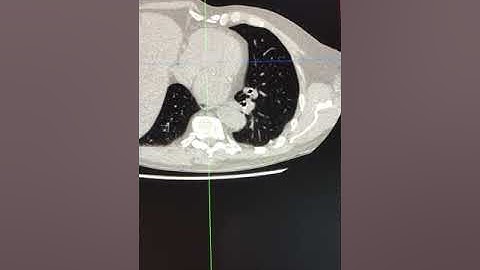

Aortic Valve Calcification: Clinical Implications and Automated Quantification by AI